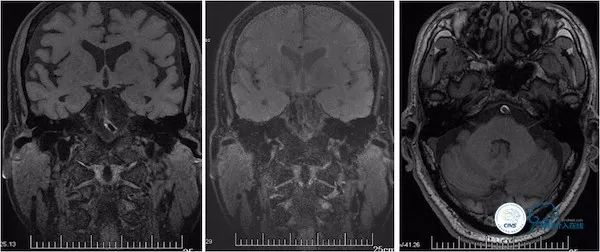

患者,男,69岁,主因“基底动脉球囊扩张术后1.5年,发作性头晕2月”入院。患者1年9个月前(2016-2)出现发作性头晕,持续数分钟后缓解,反复发作后遗留头昏沉感及走路不稳伴行走右偏,就诊附近医院,MRI示双侧小脑半球多发栓塞(图1)。

图1

MRA示基底动脉近段重度狭窄(图2)。

图2